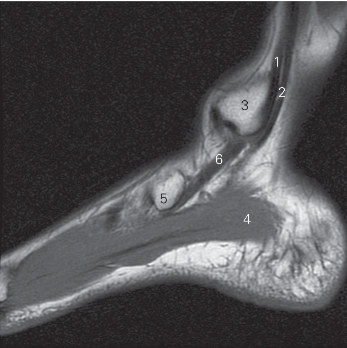

图5-56 经胫骨内髁的矢状断层MR T1加权图像

1 胫骨后肌 tibialis posterior 2 趾长屈肌 flexor digitorum longus

3 内踝 medial malleolus 4

展肌 abductor hallucis

5 舟骨 navicular bone 6 胫骨后肌 tibialis posterior